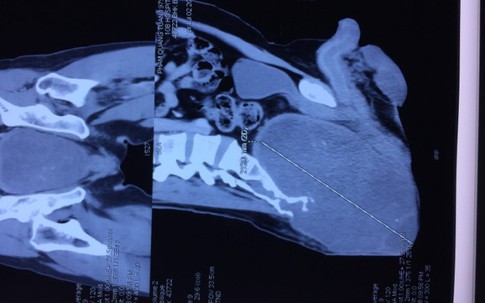

GiadinhNet - Thông tin từ Bệnh viện đa khoa Trung ương Cần Thơ cho biết, bệnh viện vừa phẫu thuật thành công ca u màng não khổng lồ cho một bệnh nhân nữ 43 tuổi. Đây là ca bệnh khó và có nguy cơ tử vong cao nếu không được chữa trị kịp thời. Bệnh nhân có thể liệt tay, chân nếu xử trí không tốt.